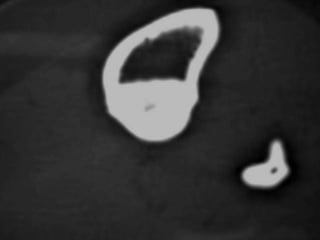

Osteoid Osteoma

• CT may detect the nidus, whereas

roentgenograms show only sclerosis.

Osteoid Osteoma - CT

• CT is more accurate than MRI.

• CT helped in confirming the diagnosis of

osteoid osteoma in 74% of cases.

• Szendroi et al reported accuracies of about

66% in the diagnosis of intra-articular lesions

and 90% in extra-articular lesions.

• To date, CT scanning is the primary

investigational tool for the definitive diagnosis

of osteoid osteoma.

• Excision of the osteoid osteoma nidus using

CT–assisted localization, a Kirschner wire

inserted into the nidus, and a biopsy punch

inserted over the Kirschner wire into the

bone.

• They recommend using a trephine 2 mm

larger than the lesion for complete removal.

CT – Guided Drilling

•

OPD procedure,

Localization of the nidus in CT Scan,

Local anesthesia,

K-wire passed into nidus,

Transferred to OT,

Short GA,

Drilling of the nidus by a cannulated drill,

Complete relief of pain.

Osteoid Osteoma • CTmay detect the nidus, whereas roentgenograms show only sclerosis.

Osteoid Osteoma -CT • CT is more accurate than MRI. • CT helped in confirming the diagnosis of osteoid osteoma in 74% of cases. • Szendroi et al reported accuracies of about 66% in the diagnosis of intra-articular lesions and 90% in extra-articular lesions. • To date, CT scanning is the primary investigational tool for the definitive diagnosis of osteoid osteoma.

CT – GuidedDrilling • • • • • • • • OPD procedure, Localization of the nidus in CT Scan, Local anesthesia, K-wire passed into nidus, Transferred to OT, Short GA, Drilling of the nidus by a cannulated drill, Complete relief of pain.